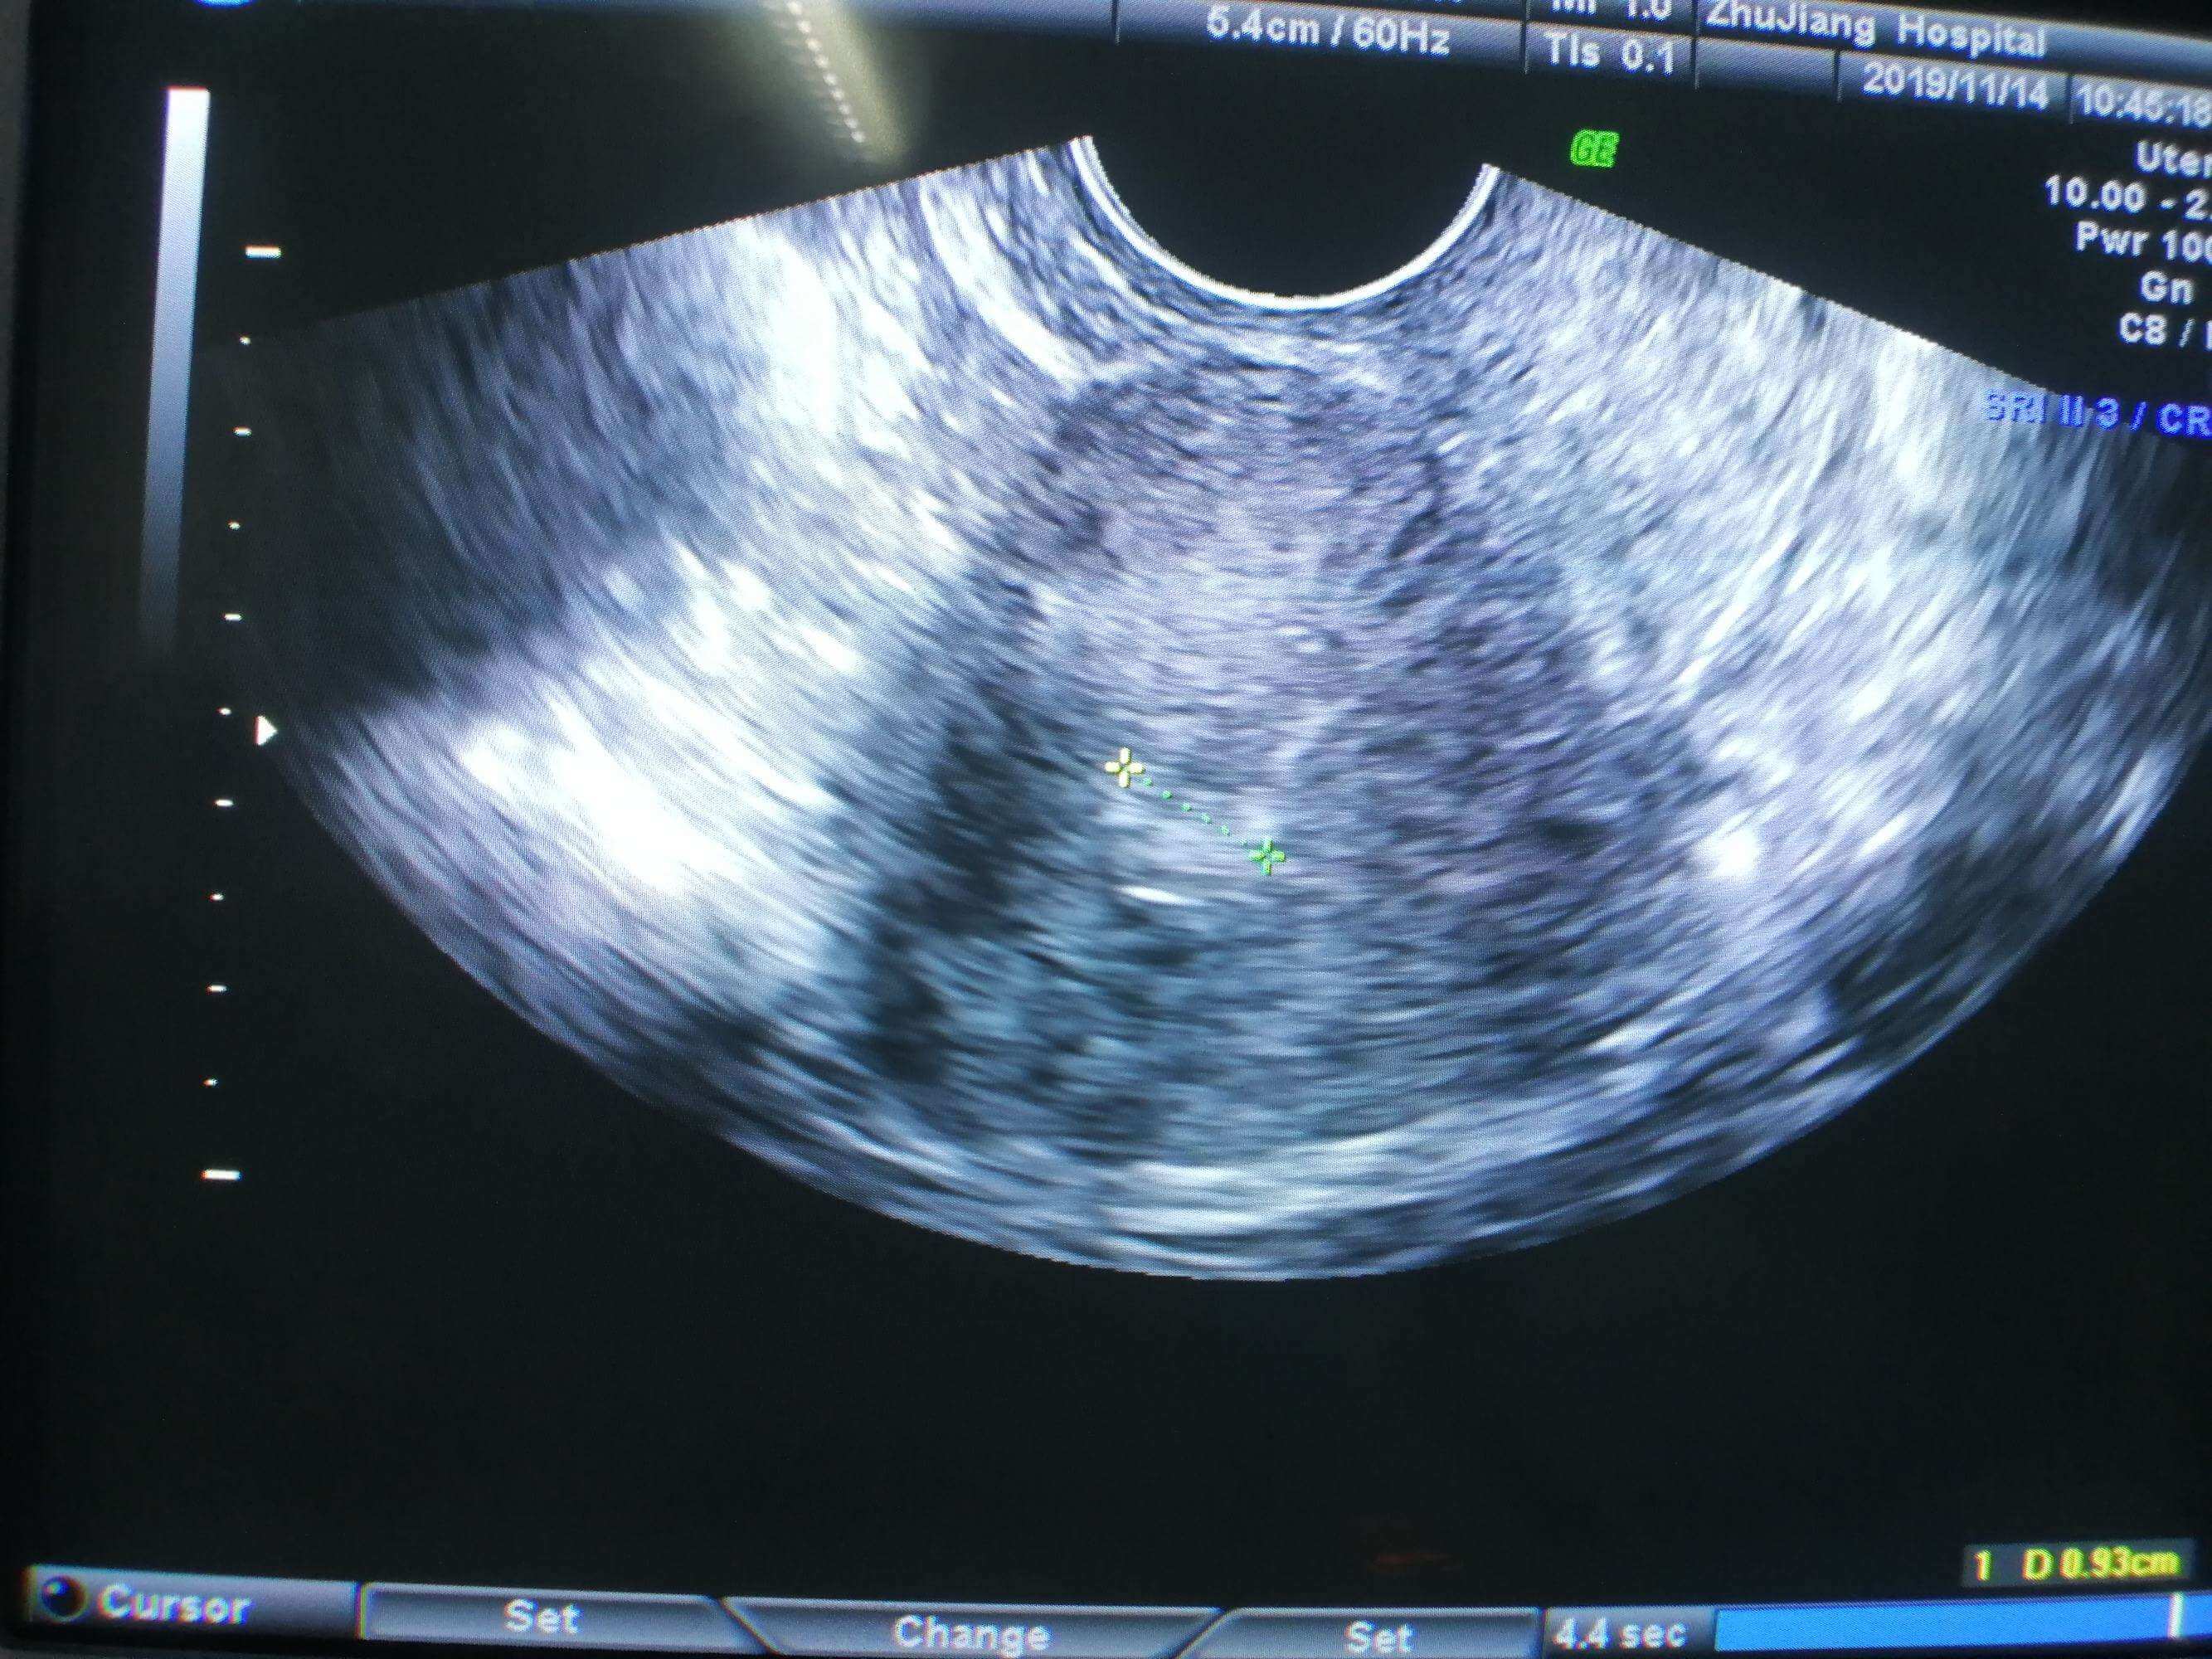

黃體期方案是什麼很多試管嬰兒患者並不知曉,其實隨著卵泡發育波理論的提出,然後在臨床上也就出現在卵泡波進行促排卵,這就是試管嬰兒黃體期方案最初出現的情況,為不孕不育患者重新打開了嶄新的促排思路。黃體期促排卵方案的基本情況B超是促排方案都少不了的,黃體期促排卵方案通過B超明確排卵或取卵術後3天左右開始,當卵泡直徑小於等於10mm的時候開始促排給藥用藥,當卵泡發育大於17mm的時候開始進行絨促性素扳機,...